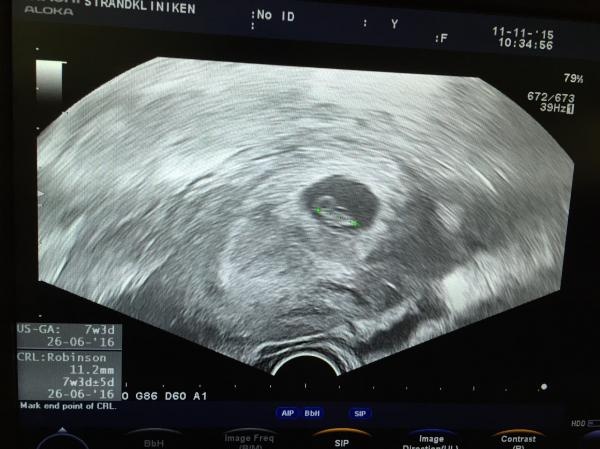

Lille plutten som förra måndagen skrämde slag på mig. Va då en hel vecka mindre än min uträkning idag 9 dagar senare en liten plutt på 11mm nästan ifatt min egna uträkning.

7+3 så mitt tips GÅ ALDRIG på tidiga VUL. Inte värt oron!

vul avklarat idag! 14,2 mm och ett litet hjärta som tickade på som bara den :) äntligen känns det på riktigt och inte som att jag bara hittat på det här! Blev framflyttad en dag så 7+5 idag :)